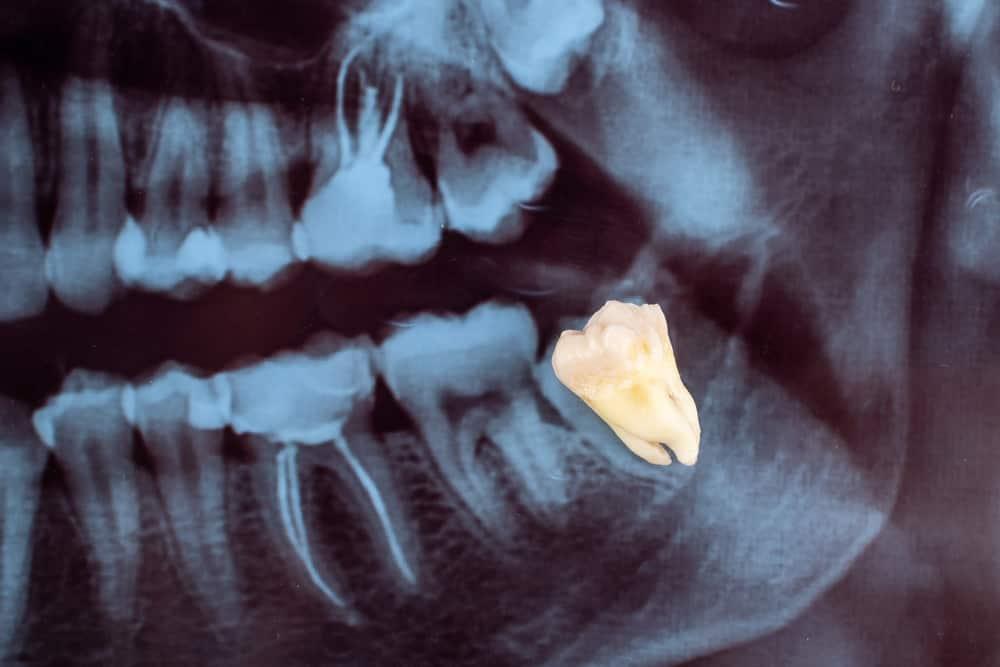

Răng khôn, hay còn gọi là răng số 8, là những chiếc răng hàm thứ ba mọc lên cuối cùng và xa nhất ở cả hai bên miệng, nằm tận trong cung hàm trên và dưới. Một người trưởng thành thường sẽ có 32 chiếc răng, bao gồm 14 chiếc răng ở hàm trên, 14 chiếc răng ở hàm dưới và 4 chiếc răng khôn mọc sau cùng, chia đều cho hai hàm.

Vì thường mọc trong độ tuổi trưởng thành nên răng số 8 được gọi với cái tên gần gũi là răng khôn. Thế nhưng, không phải chiếc răng số 8 nào cũng mọc “khôn” như tên thường gọi. Trong khi một số răng khôn mọc thẳng và không gây ra bất kỳ vấn đề gì, một số khác lại mọc ngầm, mọc lệch, gây ra các vấn đề về sức khỏe răng miệng như sưng đau, nhiễm trùng, sâu răng, bệnh nướu răng… Những chiếc răng khôn mọc bất thường này có thể cần phải nhổ bỏ hoặc áp dụng biện pháp điều trị khác.